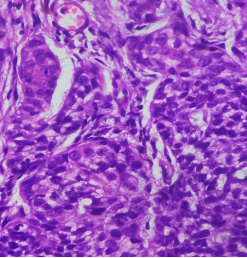

HISTOPATHOLOGY

Section H and E x400. Mass in the wall of the small intestine in a 72 year old male patient who presented with frequent diarrhoea. Make you diagnosis.